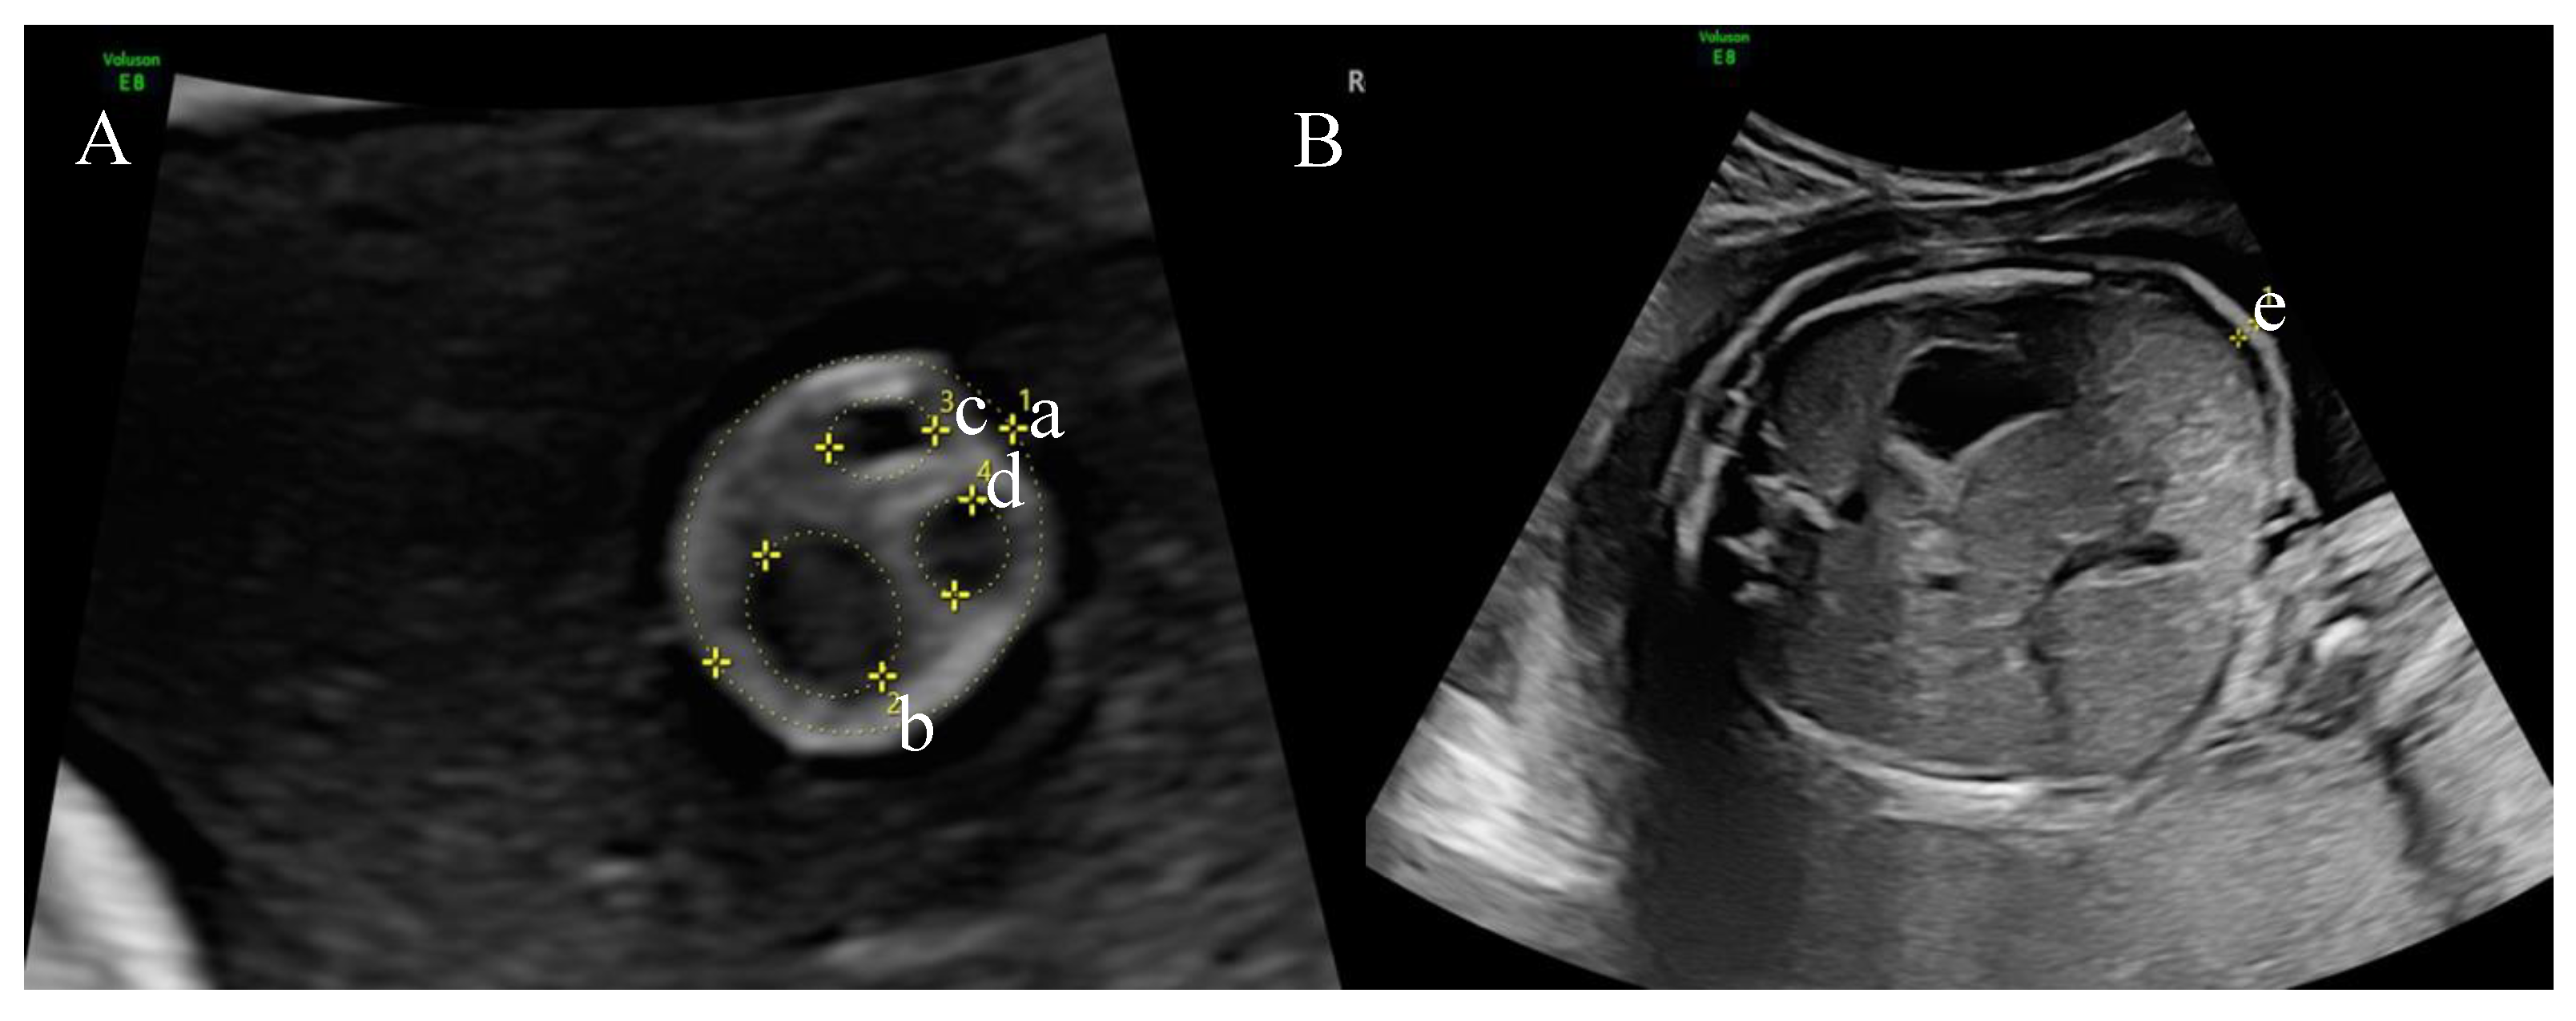

| Umbilical cord area (cm2) | 2.03 ± 0.48 | 1.86 ± 0.41 | 0.189 |

| Umbilical cord circumference (cm) | 5.05 ± 0.66 | 4.82 ± 0.57 | 0.201 |

| Umbilical cord vein (cm2) | 0.37 ± 0.13 | 0.32 ± 0.11 | 0.121 |

| Umbilical cord artery 1 (cm2) | 0.09 ± 0.11 | 0.07 ± 0.02 | 0.363 |

| Umbilical cord artery 2 (cm2) | 0.09 ± 0.13 | 0.07 ± 0.02 | 0.329 |

| Wharton jelly (cm2) | 1.46 ± 0.42 | 1.39 ± 0.35 | 0.517 |

| Abdominal skin fold (cm) | 0.32 ± 0.07 | 0.22 ± 0.07 | 0.000 |